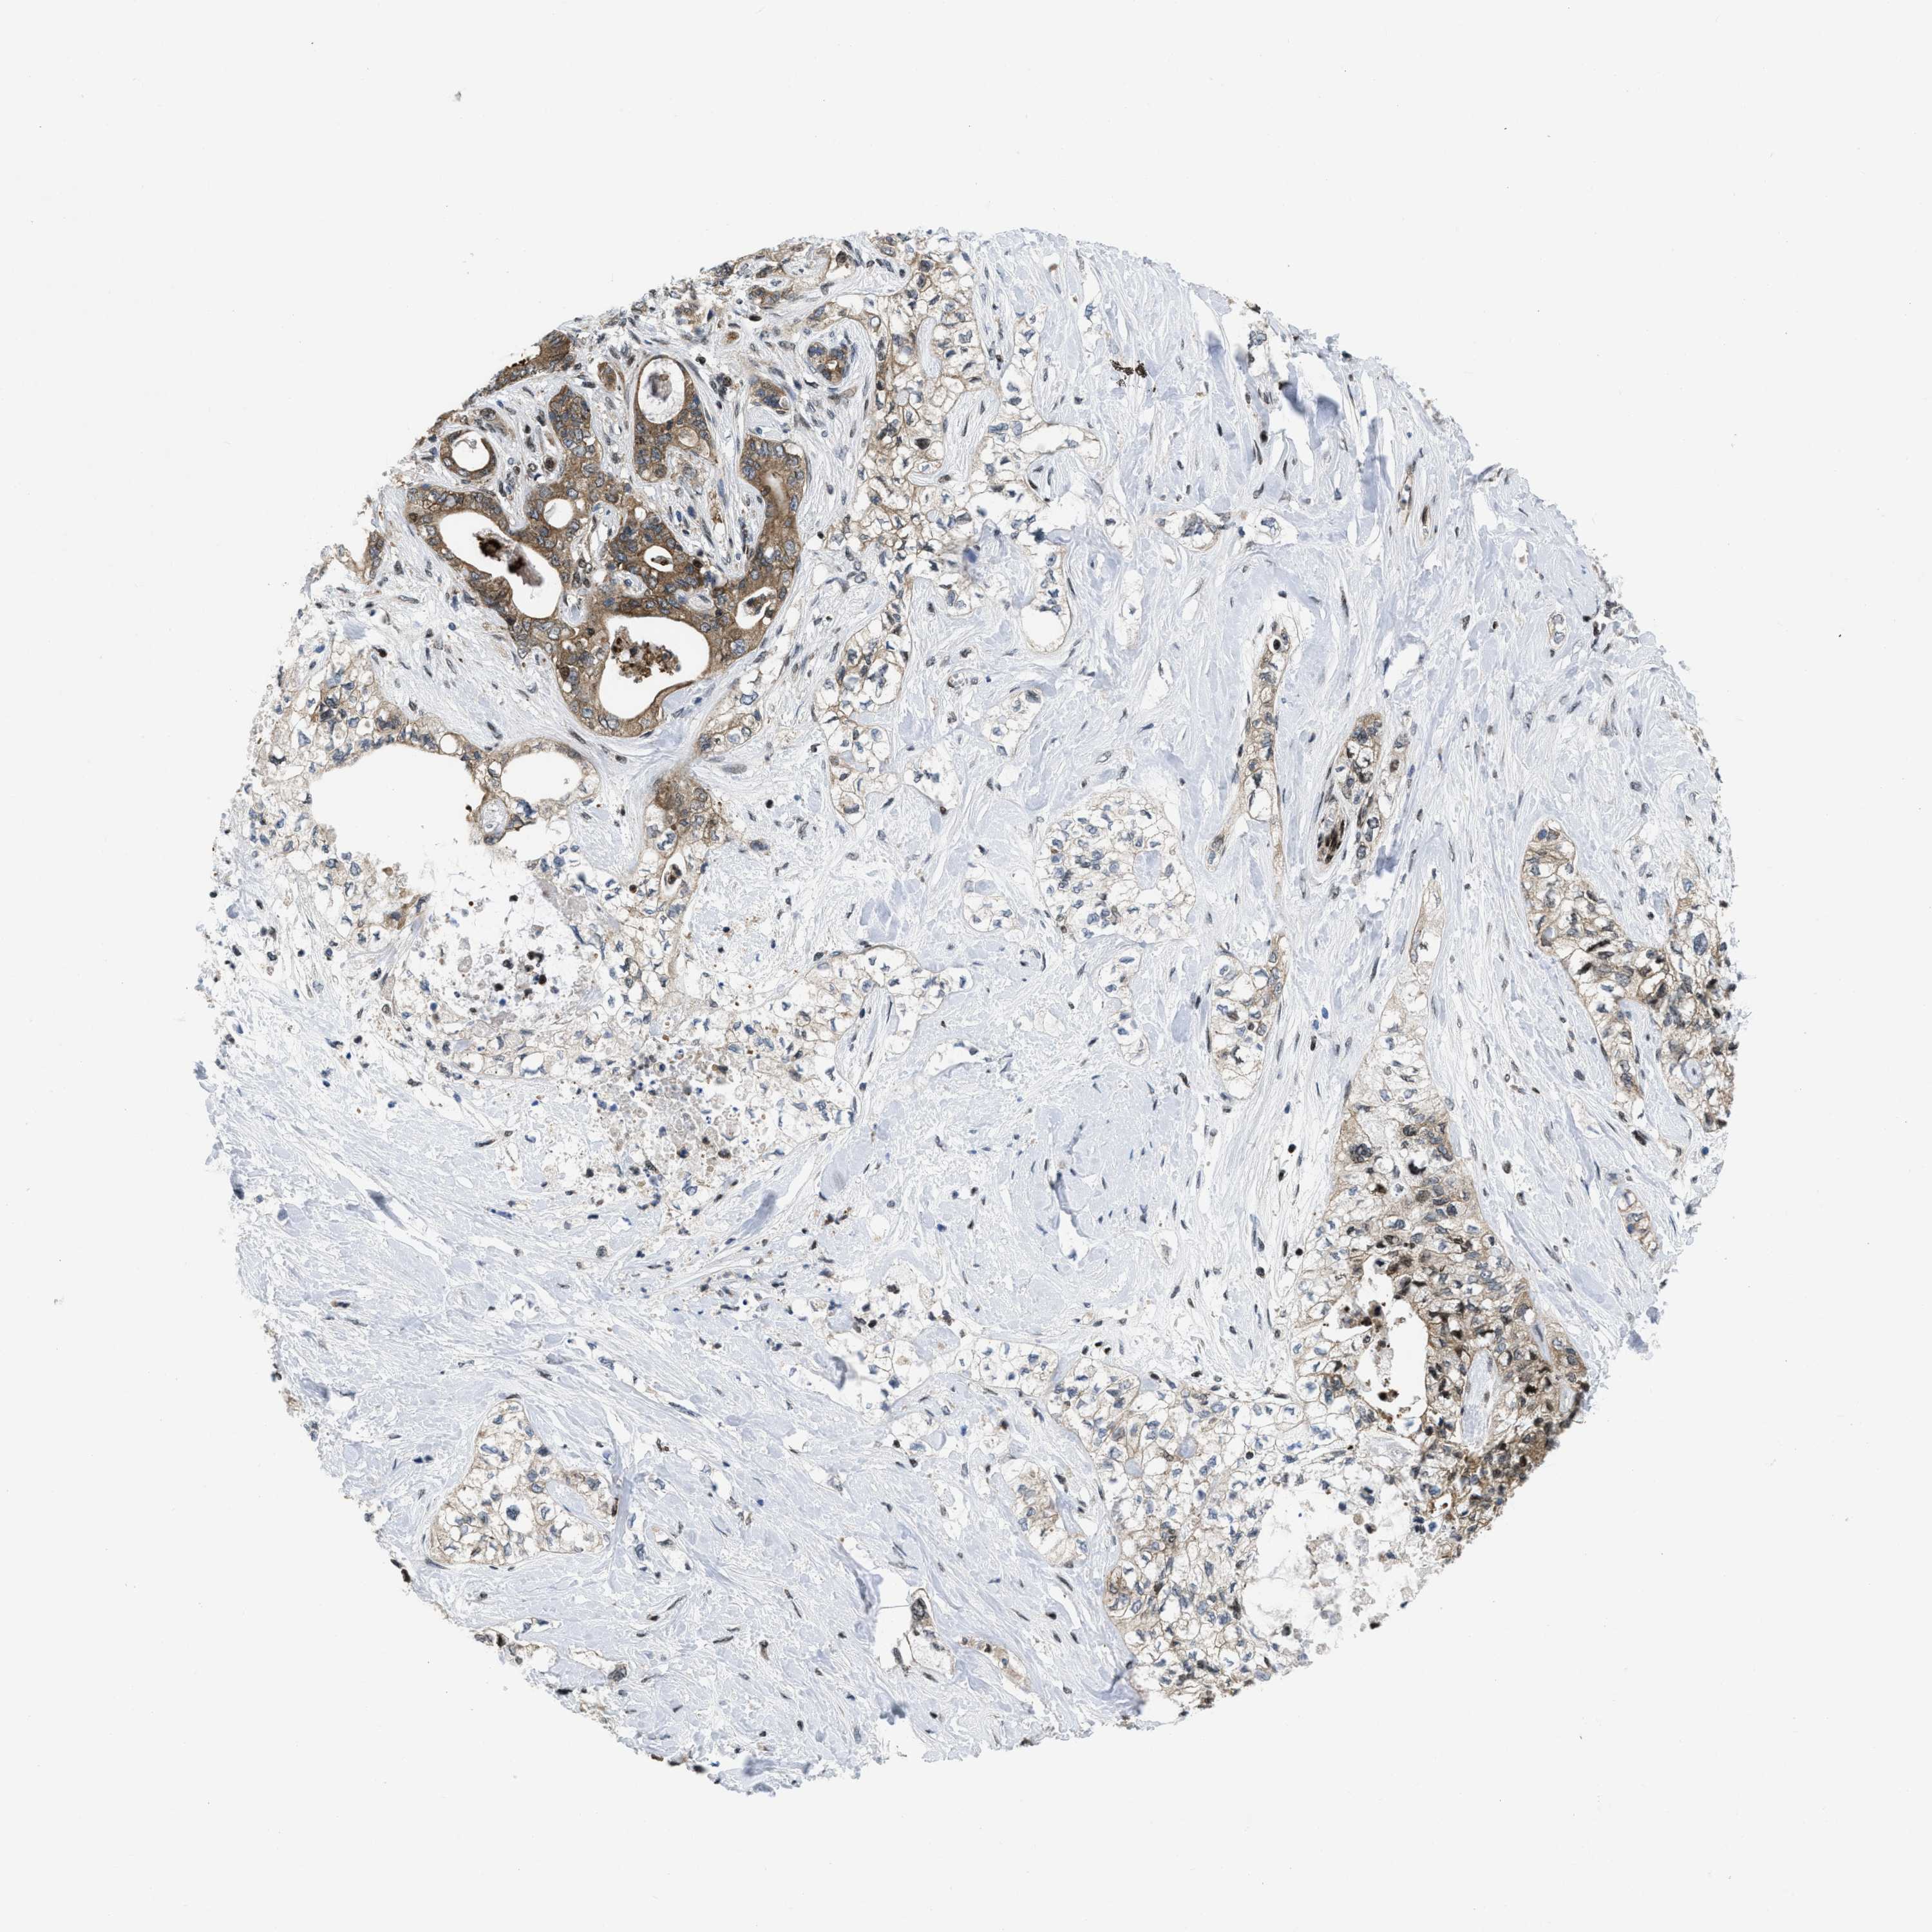

PANCREATIC CANCER - Protein expressioni

A mouse-over function shows sample information and annotation data. Click on an image to view it in a full screen mode. Samples can be filtered based on level of antibody staining by selecting one or several of the following categories: high, medium, low and not detected. The assay and annotation is described here.

Note that samples used for immunohistochemistry by the Human Protein Atlas do not correspond to samples in the TCGA dataset.

Antibody stainingi

Antibody staining in the annotated cell types in the current human tissue is reported as not detected, low, medium, or high, based on conventional immunohistochemistry profiling in selected tissues. This score is based on the combination of the staining intensity and fraction of stained cells.

Each image is clickable and will lead to virtual microscopy that enables deeper exploration of all samples and also displays staining intensity scores, fraction scores and subcellular localization as well as patient and tissue information for each sample.

Antibody HPA043236

Antibody CAB018600

Staining

High

Medium

Low

Not detected

Intensity

Strong

Moderate

Weak

Negative

Quantity

>75%

75%-25%

<25%

None

Location

Nuclear

Cytoplasmic/membranous

Cytoplasmic/membranous,nuclear

Adenocarcinoma, NOS